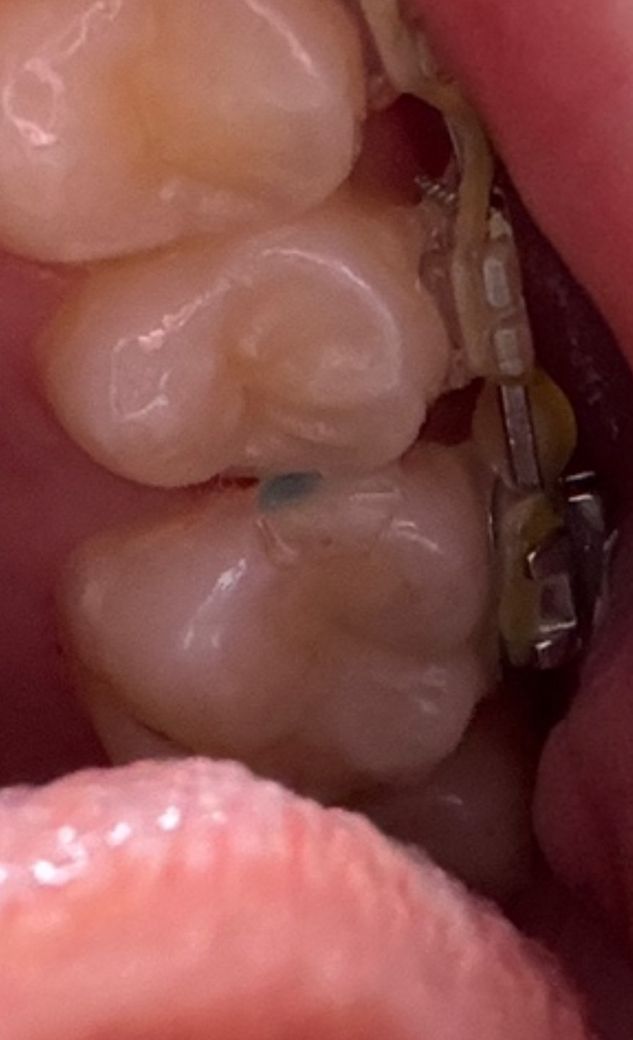

초록색으로 보이는데 어금니와 어금니사이에 이것 충치인가요?

어느날 이빨을 보았는데 어금니와 어금니사이에 저렇게 초록색 곰팡이 같은게 있어서요... 충치인지 모르겠어서요.

일반적인 충치의 양상은 아닙니다 치과용 재료로 추정되나 보다 정확한 진단을 위해 치과 가보시는게 좋겠습니다

충치는 아닌 것으로 보이며, 음식물 찌꺼기가 꺼어서 빠지지 못한 것으로 보입니다. 치실을 이용하여 제거를 해보길 권합니다.

교정을 하시는중이신거 같습니다. 치아 사이 공간을 확보하려고 일부러 해놓은거 같습니다. 충치는 아니니 걱정하지 않으셔도 될것같습니다.